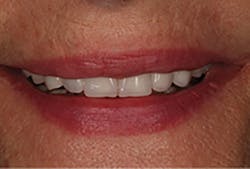

At the third clinical visit, the provisionals were removed, the preparations cleaned, and the final restorations cemented, without the need for contact or occlusal adjustments (figure 11). The patient was delighted with the outcome, which precisely duplicated the proposed treatment plan that was the basis for the provisional restorations she’d previously worn and the definitive restorations (figure 12).

Figure 13: Postoperative facial view of the six CAD/CAM crown restorations

Figure 14: View of the patient’s original smile appearance, which was greatly enhanced by the CAD/CAM restorations, as planned in Figure 5; duplicated and evaluated in provisionals, as shown in Figure 8; and precisely created in the definitive treatment in Figure 13